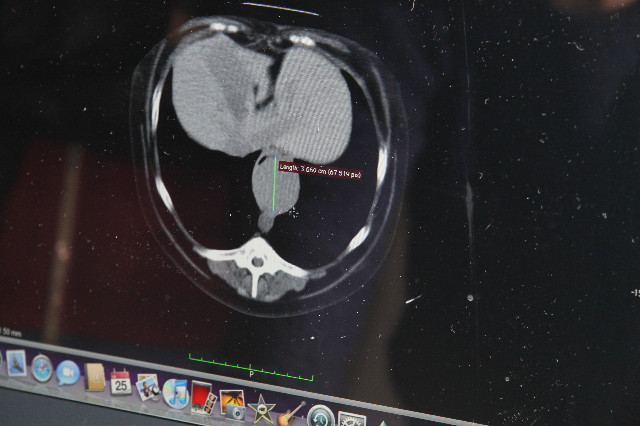

食道内に直径最大3.6cmくらい、長さは7cmくらい?の腫瘍があることがわかりました。(後日、腫瘍はほぼ円形であることがわかりました。)

腫瘍が大きなところでは、空間はほんの数ミリしかありません。

画像の、緑の線が腫瘍の最大直径(36mm)です。

その○の、11時方向に黒い部分がありますよね?

それがべべちゃんの食道の空間部分です。